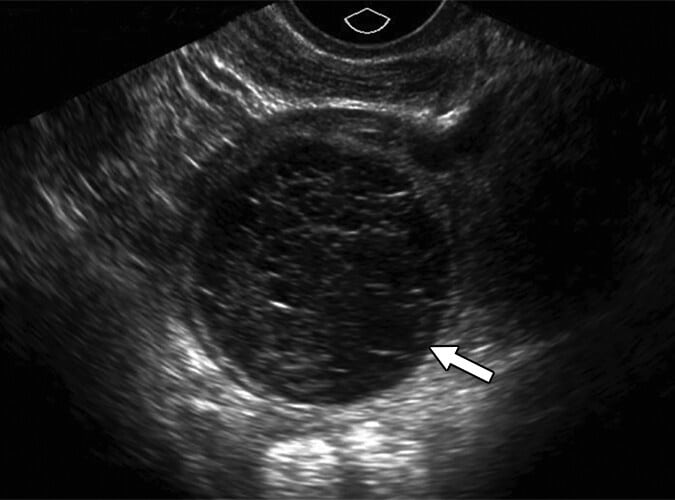

Lesões císticas são aquelas formadas total ou majoritariamente por líquido. A primeira etapa da avaliação é verificar se existe septo completo: quando presente, a lesão classifica-se como multilocular; quando ausente, é considerada unilocular.

Em seguida, deve-se identificar se há componente sólido aderido à parede ou a algum septo, lembrando que estruturas excluídas da definição de sólido não devem ser contabilizadas.

Cisto unilocular sem componente sólido

Avalia-se inicialmente um cisto unilocular sem componente sólido pela aparência da sua parede interna. Quando essa parede é lisa, analisa-se o conteúdo do cisto:

- Se for totalmente anecoico, classifica-se como cisto simples;

- Caso apresente ecos internos ou septações incompletas, considera-se um cisto unilocular não simples.

Na classificação O-RADS, tanto os cistos simples quanto os não simples com menos de 10 cm recebem categoria 2, e sua conduta depende do tamanho e do estado menopausal da paciente. Quando o cisto atinge 10 cm ou mais, classifica-se como O-RADS 3.

Ademais, se a parede interna apresentar irregularidades menores que 3 mm projetadas para dentro da cavidade cística, qualquer cisto unilocular sem componente sólido é automaticamente classificado como O-RADS 3, independentemente de seu conteúdo ou do status menopausal.